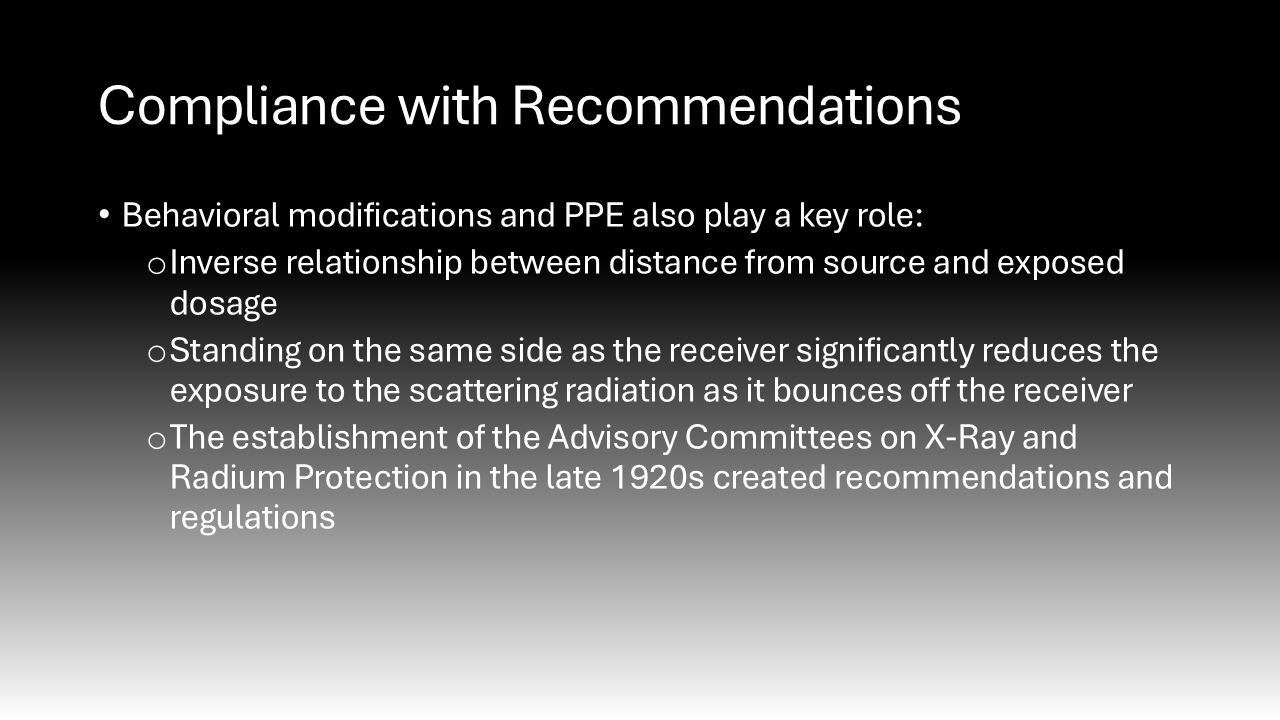

Behavioral modifications and personal protective equipment also play a key role in risk mitigation for those exposed to intraoperative radiation.4 When surgeons stand further away from the radiation source, they are exposed to an inversely proportionally decreased dose of radiation.4 Additionally, simply standing on the same side as the receiver significantly reduces the exposure to the scattering radiation as it bounces off the receiver.4 Following the establishment of the Advisory Committees on X-Ray and Radium Protection in the late 1920s, recommendations and regulations requiring the availability and use of lead protection devices and shielding devices have significantly curbed the negative effects of intraoperative scatter radiation exposure.16 These policies were adopted by the Occupational Health and Safety Administration (OSHA) and local hospitals, such as Stony Brook University Hospital.17–20 Lead aprons can reduce exposure by up to 90%, lead collars can reduce thyroid exposure 9-fold, lead gloves can reduce hand exposure by 75%, lead glasses can reduce exposure by up to 70%, and shields can offer significant reductions.4,21